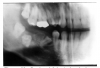

Congenital hypodontia most commonly affects the third molars, the permanent maxillary lateral incisors and the maxillary and mandibular premolars. Frequently, hypodontia is bilateral. Figure 28 is an example of a patient with congenital hypodontia, affecting the mandibular second premolars bilaterally, the left mandibular first permanent molar, and retention and ankylosis of the mandibular second deciduous molars.

Figure 28 - Congenital Hypodontia

Figure 28